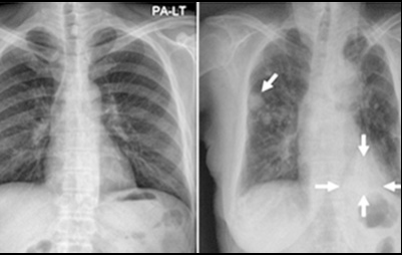

이번 기사에서는 폐암 초기 증상에 대해 자세히 정리해 알려 드리겠습니다 . 폐암은 국내암 사망률 1 위로, 과거에는 흡연이 폐암의 주된 원인 이었지만 , 현재는 비흡연 폐암 환자도 대폭 증가했습니다 . 폐암은 의학 기술로 발달하여 생존율이 높아지고 있습니다 . 폐암의 초기 증상은 무엇인가를 알아보겠습니다.

폐암의 초기 증상